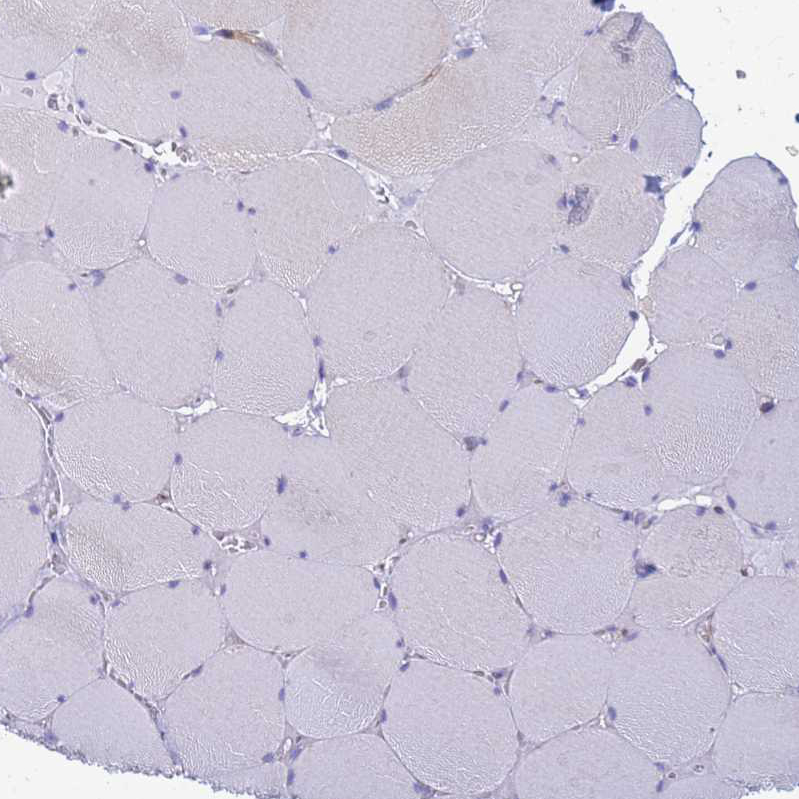

Immunohistochemistry analysis in human placenta and skeletal muscle tissues using HPA044933 antibody. Corresponding COBLL1 RNA-seq data are presented for the same tissues.